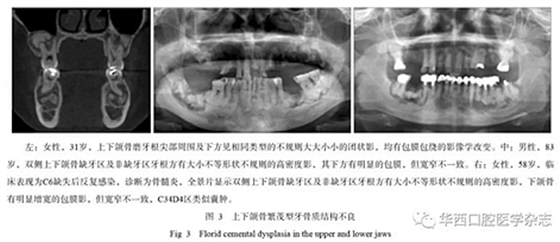

2.4 上、下頜骨均發(fā)生

這類改變可稱為“繁茂型牙骨質(zhì)結(jié)構(gòu)不良”,簡單地理解就是在上下頜骨只要有牙的地方都可以發(fā)生[1]。由于牙骨質(zhì)小體無序混亂的生長,導(dǎo)致牙和頜骨出現(xiàn)相關(guān)的血供問題,臨床上常常發(fā)生骨髓炎改變,甚至頜骨局部膨大類似腫瘤,病程很長,治療效果也不好。繁茂型牙骨質(zhì)結(jié)構(gòu)不良的影像學(xué)特征是上下頜骨均出現(xiàn)多數(shù)的高密度小團(tuán)片狀影,周圍有包膜包繞,骨皮質(zhì)可變薄,繼發(fā)感染時可出現(xiàn)類似死骨的征象,而向外膨脹的時候就表現(xiàn)為類似腫瘤樣改變(圖3)。